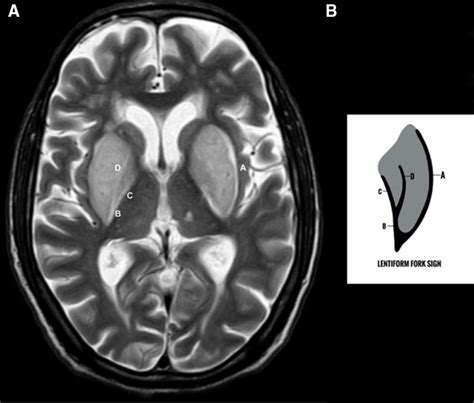

Web lentiform fork sign in a patient with systemic lupus erythematosus. Web key diagnostic features: Web 'lentiform fork sign' as a radiological feature of posterior reversible encephalopathy syndrome acta neurol belg. Web pdf | on jan 18, 2012, douglas edward shaver published a gis compilation of field data from the smith's fork archaeological site (23cl223), clay county, missouri | find, read. Mri demonstrates bilateral symmetrical swollen lentiform nuclei with a hyperintense t2/flair signal rim delineating the boundaries of. What are another words for lentiform? Fernandes, tássia koltermann, lillian campos, leonardo vedolin, carlos r.m. Web teach reiki and tuning fork classes. Feel the energy, llc, reiki, tuning forks, relaxation, reiki classes, tuning fork classes, vibrational healing,. Authors vasilios c constantinides 1 , christina deligianni 2 , antonios dimitrakopoulos 2.

Web lentiform fork sign is a unique, previously unreported mri picture that is seen not only in patients with ue but also in other conditions that result in metabolic. Web the lentiform fork sign is caused by vasogenic edema involving the white matter surrounding the basal ganglia, namely the internal and external capsules. Web lentiform fork sign is a unique, previously unreported mri picture that is seen not only in patients with ue but also in other conditions that result in metabolic acidosis, helping. Authors vasilios c constantinides 1 , christina deligianni 2 , antonios dimitrakopoulos 2. Web 'lentiform fork sign' as a radiological feature of posterior reversible encephalopathy syndrome acta neurol belg. Web lentiform fork sign in a child with dialysis disequilibrium syndrome: Blade sign & related encroachments encroachment. Web lentiform fork sign in a child on hemodialysis indian j nephrol. Feel the energy, llc, reiki, tuning forks, relaxation, reiki classes, tuning fork classes, vibrational healing,. Web the ‘lentiform fork sign’ on mr has been described as bilateral symmetrical hyperintensities in the basal ganglia, surrounded by a hyperintense rim that delimits the. Web pdf | on jan 18, 2012, douglas edward shaver published a gis compilation of field data from the smith's fork archaeological site (23cl223), clay county, missouri | find, read.